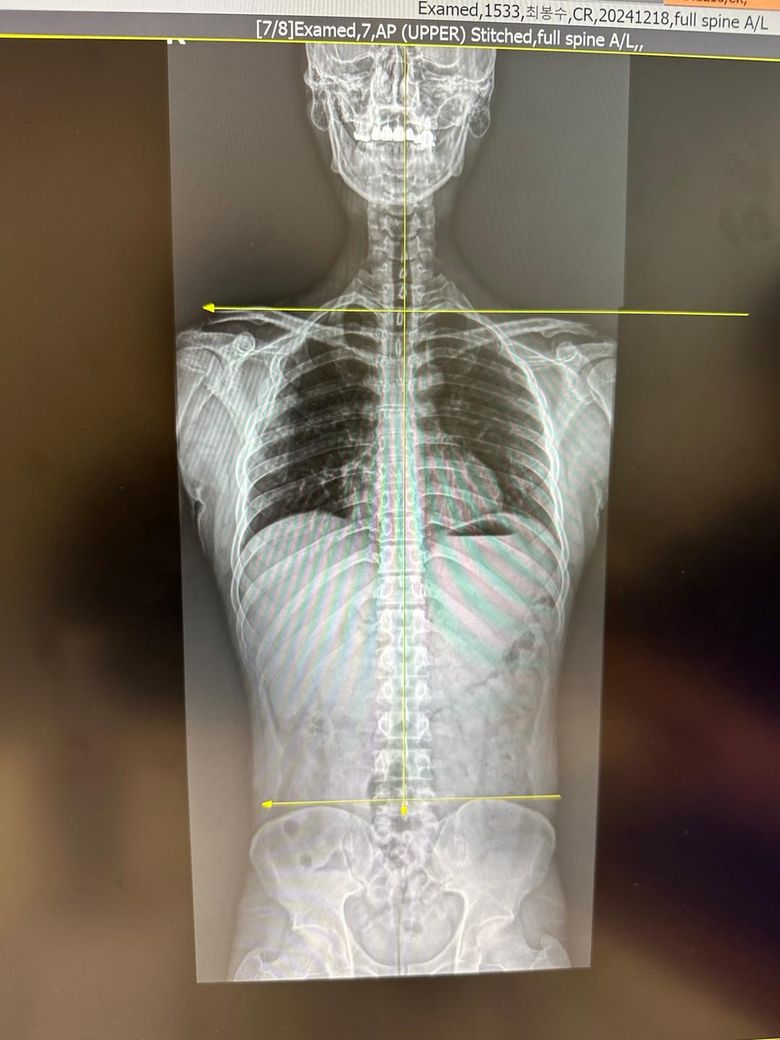

한쪽 어깨 찝힘이 발생해서 엑스레이를 찍어봤습니다..

엑스레이 사진상에 보시면 제 기준 오른쪽(사진 기준 왼쪽) 어깨가 찝히는 상황이 자주 발생합니다.

특히 운동을 할때 오른쪽 어깨쪽이 짧아져 있고, 미는 운동을 할때에도 오른쪽만 불편감을 호소하게 됩니다.

그래서 엑스레이를 찍어보니 사진과 같이 양쪽 어깨 길이가 다르고, 어깨관절이 견봉쪽에 촥 달라붙어있어서 찝히는 느낌이 드는게 아닌가 합니다..

x-ray 상 골반틀어짐과 척추, 머리 등 신체 전반적인 불균형이 있어보입니다.